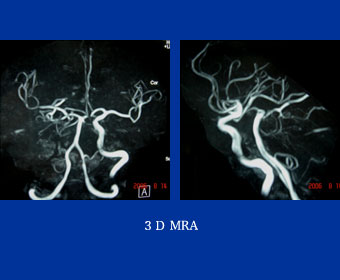

症例8

58歳 男性

【主 訴】

左間歇性跛行(150m)

【起始・経過】

平成18年1月より間欠性跛行出現。

平成18年3月近医受診しASOと診断され、Cilostazolにて保存的に加療するも改善なし。

6月当院紹介受診。

【既往歴】

胃潰瘍

54歳 脳梗塞(内服)

高血圧(+) 糖尿病(−) 喫煙歴(10本×30年)

ABI:右1.0 左0.6

【治療計画】

Bilateral CIA Stenting (Kissing stent with Palmaz stent)

症例8 MRA